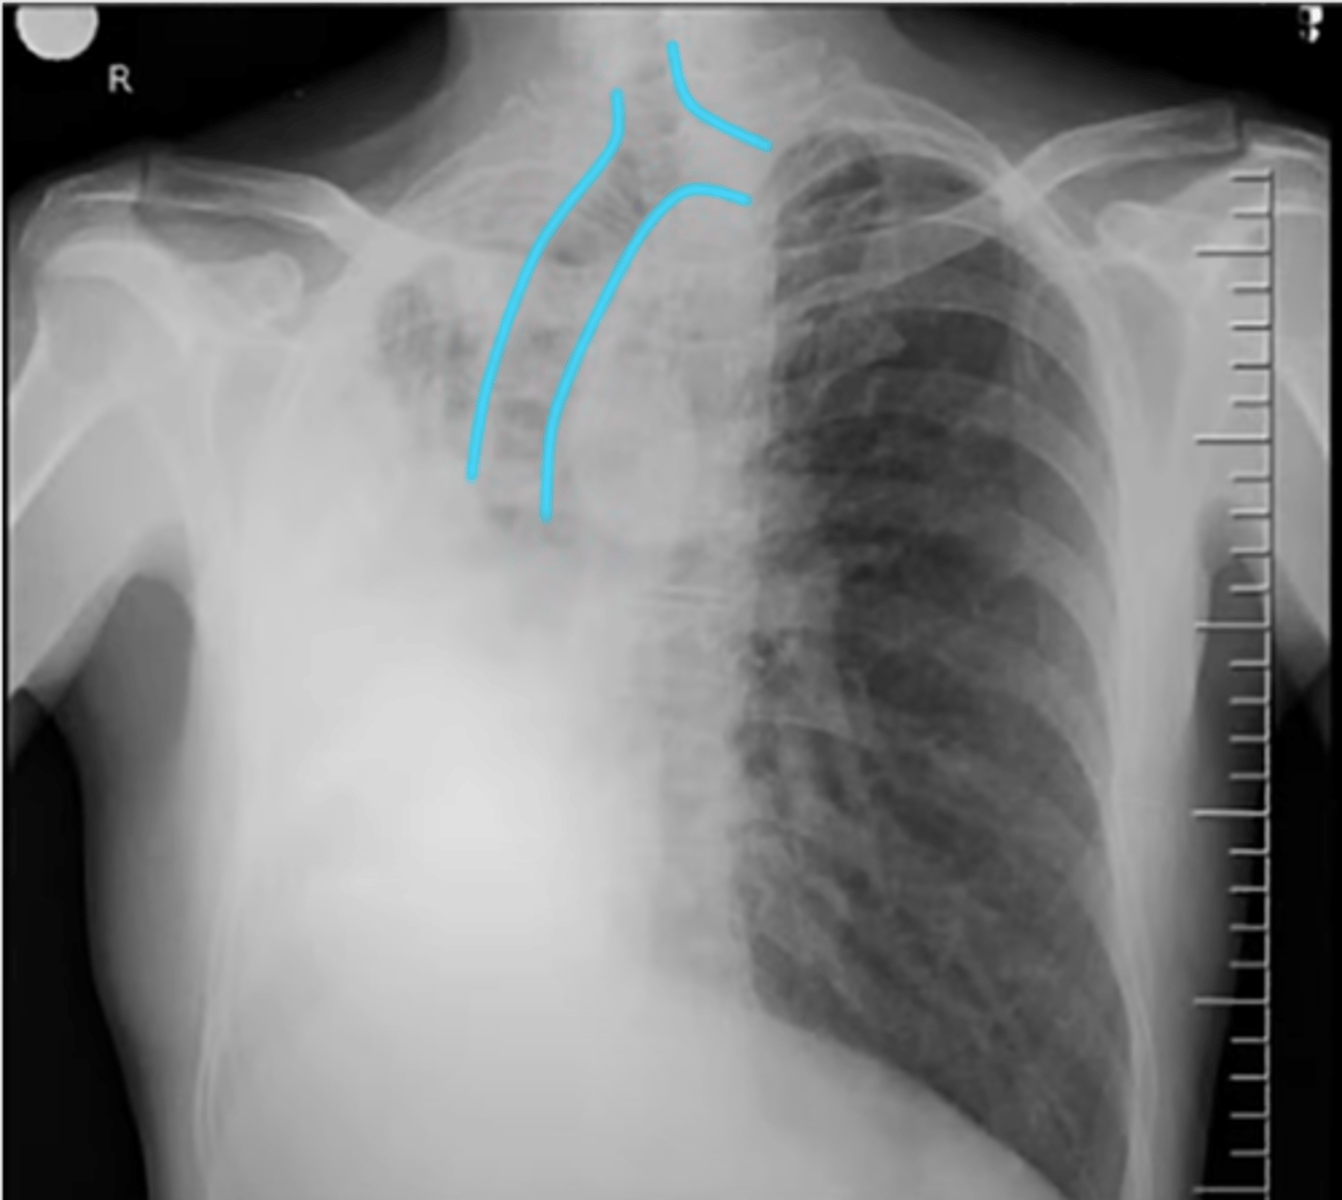

C: cardiac silhouette and mediastinum

(PICTURE ON LEFT)

Pulmonary edema appearance

-thoracic aorta is enlarged

thoracic aortic aneurysm appearance on XR

-widened mediastin and pleural effusion

thoracic aortic dissection